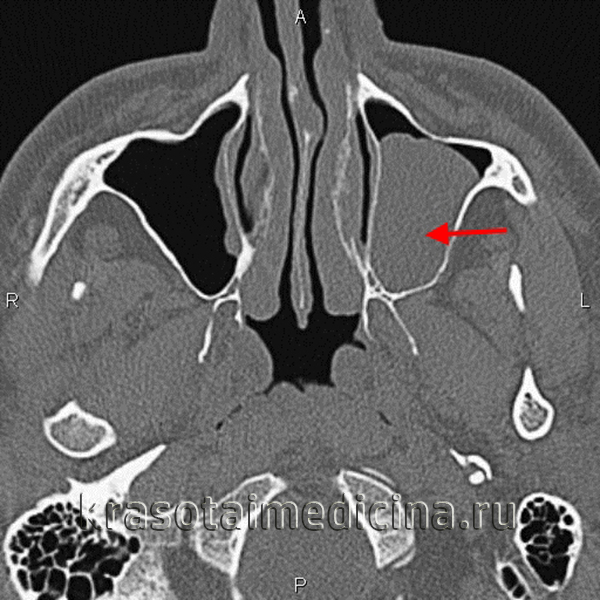

3. КТ при ювенильной ангиофиброме:

• КТ с КУ:

о Интенсивно усиливающееся мягкотканное образование возле КНО с распространением в соседние отделы носоглотки и КНЯ

о ± снижение пневматизации основной пазухи («запертое» отделяемое и опухолевый инфильтрат)

• «Костная» КТ:

о Ремоделирование костей ± деструкция

о Выбухание задней стенки верхнечелюстной пазухи кпереди

о Расширение ипсилатеральных отделов полости носа и КНЯ

5. Ангиография при ювенильной ангиофиброме:

• Традиционная ангиография обычно выполняется во время эмболизации перед операцией

• Интенсивное контрастирование капилляров опухоли, кровоснабжаемой расширенными ветвями НСА:

о ВВЧА и нисходящая глоточная артерия (ветви НСА): наиболее типичные питающие сосуды

о Внутренняя сонная артерия (ВСА): при распространении в основание черепа или поражение кавернозных синусов

о Возможно кровоснабжение ветвями контрлатеральной НСА